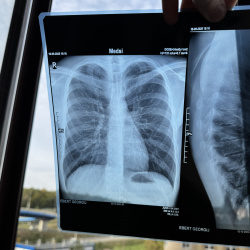

Добрый день, справа уменьшение объёма S3, инфильтрация,   подозрение на ЗНО бронха?